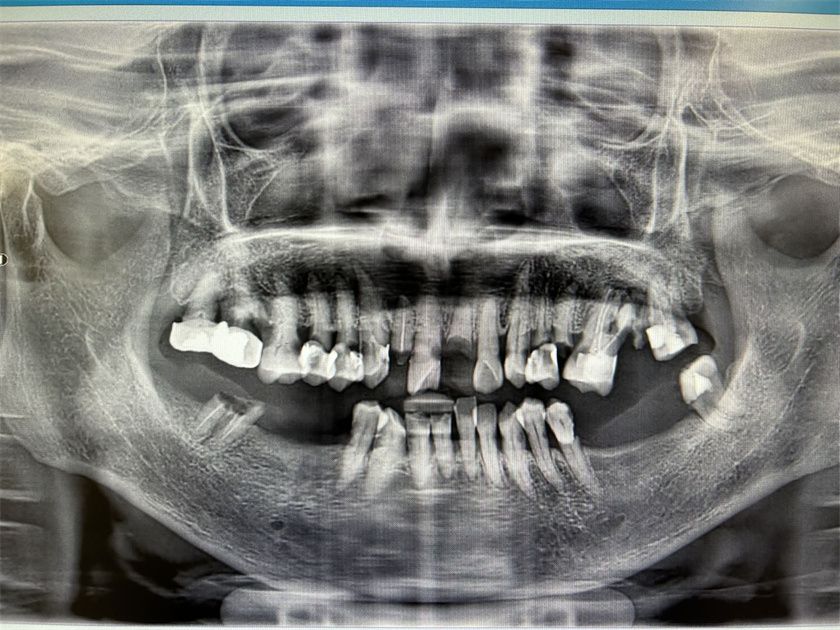

近日,四川泰康医院口腔科接诊了一位年过八十的女性患者。老人近几年,嘴里多颗牙齿开始松动,最初以为是高龄原因引起的,没有特别在意。然而近几个月,松动的牙齿和残根开始剧烈疼痛,甚至牙龈开始红肿,导致患者吃不下饭、睡不好觉,严重影响了生活质量,遂决定前往四川泰康医院就医。

口腔科医生检查后发现患者多颗牙为重度牙周炎,还有几颗牙齿龋坏严重到只剩下残根,这几颗牙属于必须拔除,才能达到治疗效果。